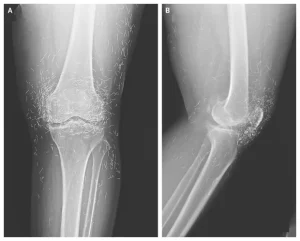

Doctors Stunned After Looking At This X-Ray Of Woman Suffering Joint Pain

A routine X-ray revealed a shocking surprise: hundreds of tiny gold needles embedded in the knees of a 65-year-old woman with severe joint pain.

Acupuncture involves inserting thin needles at specific points to relieve pain, but in this case, gold needles were intentionally left in her tissue for continuous stimulation.